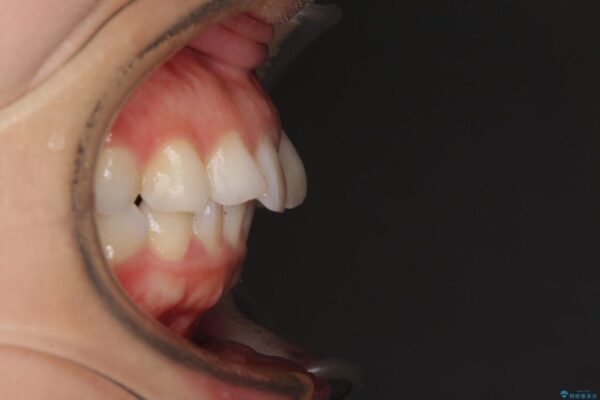

口元の閉じにくさと、奥歯の咬み合わせを気にして来院された患者様です。

左下の大臼歯2本が顕著に舌側に傾斜しているため、まずは奥歯の咬み合わせを改善をし、その後上下左右の第1小臼歯4本を抜歯することで口元を引っ込めながら整えることとしました。

治療前

• 【モニター】出っ歯と咬み合わせを改善 ワイヤー装置の抜歯矯正 治療前画像